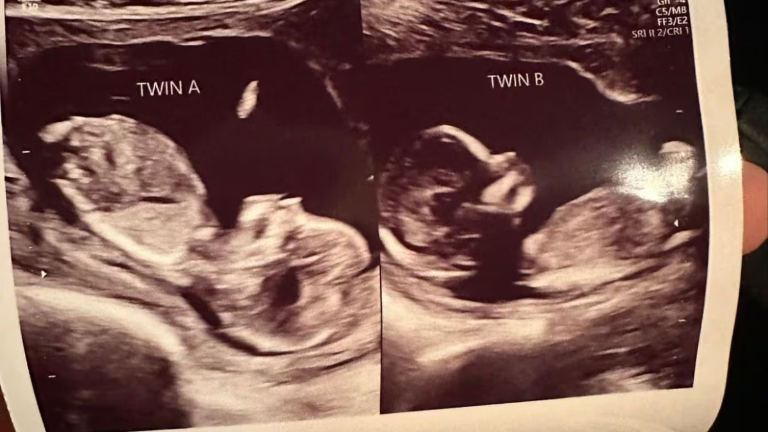

Durante un ultrasonido de rutina en mayo, la masajista terapéutica y madre de tres hijos, se enteró no solo de que esta vez tendría mellizos, sino que cada feto estaba presente en cada uno de sus úteros.

"Lo que probablemente sucedió es que ovuló de manera separada y un óvulo bajó por cada trompa de Falopio, es decir, bajó a cada lado del útero, y luego los espermatozoides viajaron hacia cada útero por separado y la fertilización se produjo separadamente", dijo al programa "Good Morning América" de ABC Shweta Patel, la ginecobstetra que atiende a Hatcher en el Centro de Mujeres e Infantes de la Universidad de Alabama, en Birmingham.